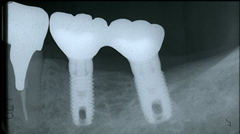

インプラントを埋入する部位の歯肉を開き、顎の骨にインプラントを埋入します。インプラントが骨にしっかり結合するまで約3ヶ月程度待ちます。 この間、必要に応じて仮歯を入れることもできますので、日常生活に差し支えありません。